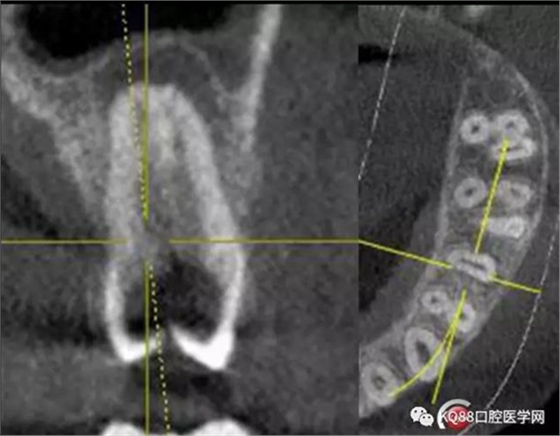

一個上6,常規(guī)的拍片,同上面的方法,根管口定位,乍一看三個根管,但是仔細(xì)研究,發(fā)現(xiàn)近中頰根,兩個根管口的C型根管,心理明了以后開始常規(guī)操作。

第一開髓后,只看見三個根管,于是進(jìn)行三個根管的預(yù)備,然后按照髓底解剖圖,進(jìn)行Mb2探查,近中頰根與腭根連線,遠(yuǎn)中頰根向其做垂直線,一般都在這條線附近,于是我開始去髓底白色鈣化,終于找到了Mb2,有鈣化,但是疏通后,到達(dá)根方,于是拍攝插針片。

四個根管成型,只是近中兩個根管融合為一個,典型的C型根管。最后開始根充,射片。